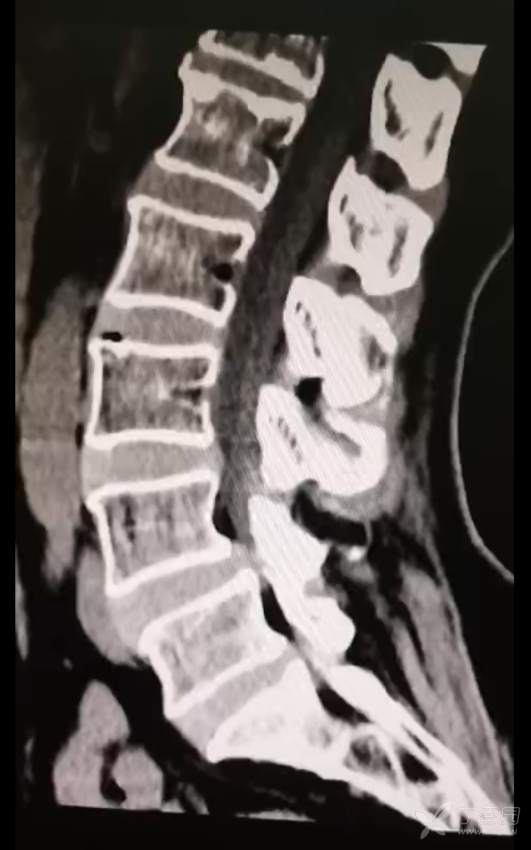

黄骨头脊柱内镜——腰4-5椎管狭窄侧路减压一例